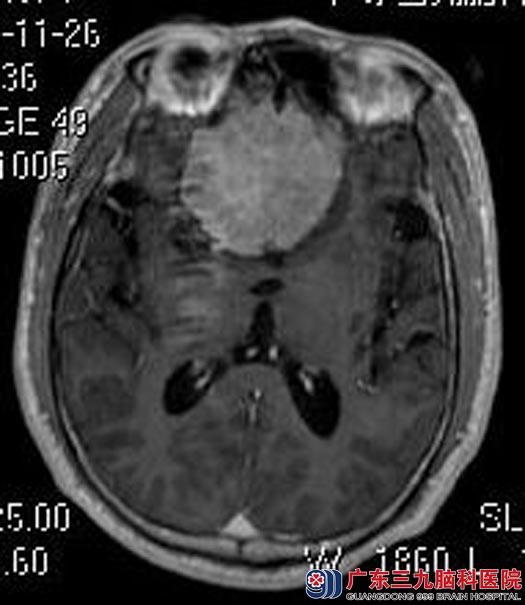

入住广东三九脑科医院综合神经外科,头颅MR检查提示:前颅窝底示一团块状占位性病变,大小约5.5cm×5.2cm×3.4cm,考虑脑膜瘤;头颅CTA检查提示:双侧大脑前动脉A1、A2段受压向后上方移位,双侧大脑前动脉额极支被病灶包绕。

由鲁明主任主刀,在全麻下行经颅底鞍结节脑膜瘤切除术,显微镜下见肿瘤与右视神经及右颈内动脉粘连较紧,视交叉及右视神经受肿瘤压迫,垂体柄受压右移,显微镜下分离肿瘤与神经、肿瘤与血管、肿瘤与垂体柄,解剖保留双侧视神经、神交叉,双侧颈内动脉、双侧大脑前动脉,手术过程顺利。

▲术前